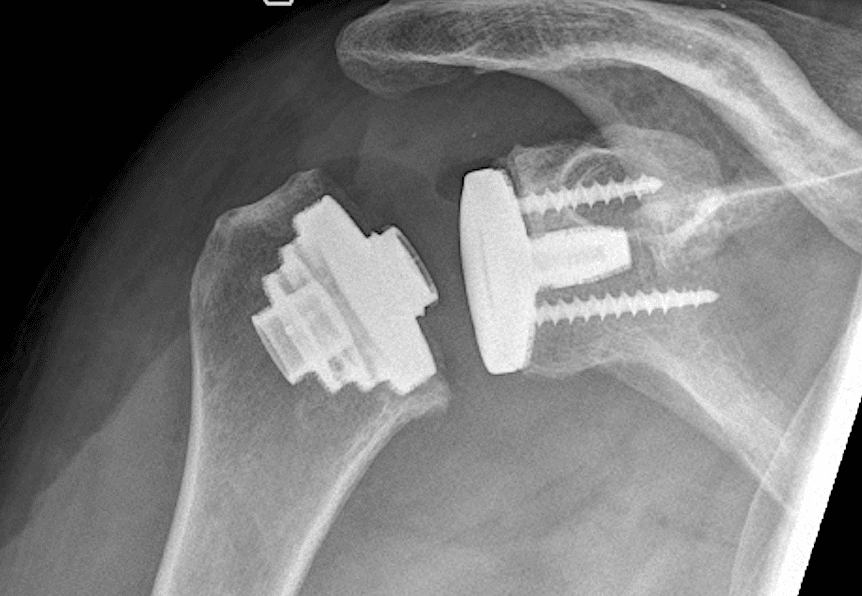

Eine Schulterprothese ersetzt das natürliche Schultergelenk – teilweise (Teilprothese) oder vollständig (Totalendoprothese). Je nach Schädigung von Knochen, Knorpel und Sehnen kommen unterschiedliche Prothesenformen zum Einsatz:

Anatomische Schulterprothese: Nachbildung des natürlichen Gelenks

Inverse (umgekehrte) Schulterprothese: Besonders geeignet bei Sehnenschäden (Rotatorenmanschettenruptur)

Hemiprothese: Ersatz nur des Oberarmkopfes

Es gibt zwei Arten von Schulterprothesen, bestehend aus je mindestens drei Komponenten.

Die anatomische Schulterprothese besteht aus

1. Einem Anteil des Oberarmes

2. Einem künstlichen Oberarmkopf

3. Und einer Gelenkpfanne

Die inverse Schulterprothese ebenfalls aus

1. Einem Oberarmanteil

2. Einem Gelenksanteil

3. Sowie einer in die Gelenkpfanne geschraubte Glenosphäre

Erstere, anatomische, wird vorallem eingesetzt bei der primären Arthrose mit erhaltener Rotatorenmanschette, leztere, inverse, bei ausgedehnten Gelenkszerstörungen und Rotatorenmanschettendefekten.

Beide Prothesen könne sowohl in einer biologischen Variante (Einwachsen den bestehenden Knochen) sowie in einer zementierten Variante (Fixierung der Prothese im Knochen durch Knochenzement) verwendet werden.